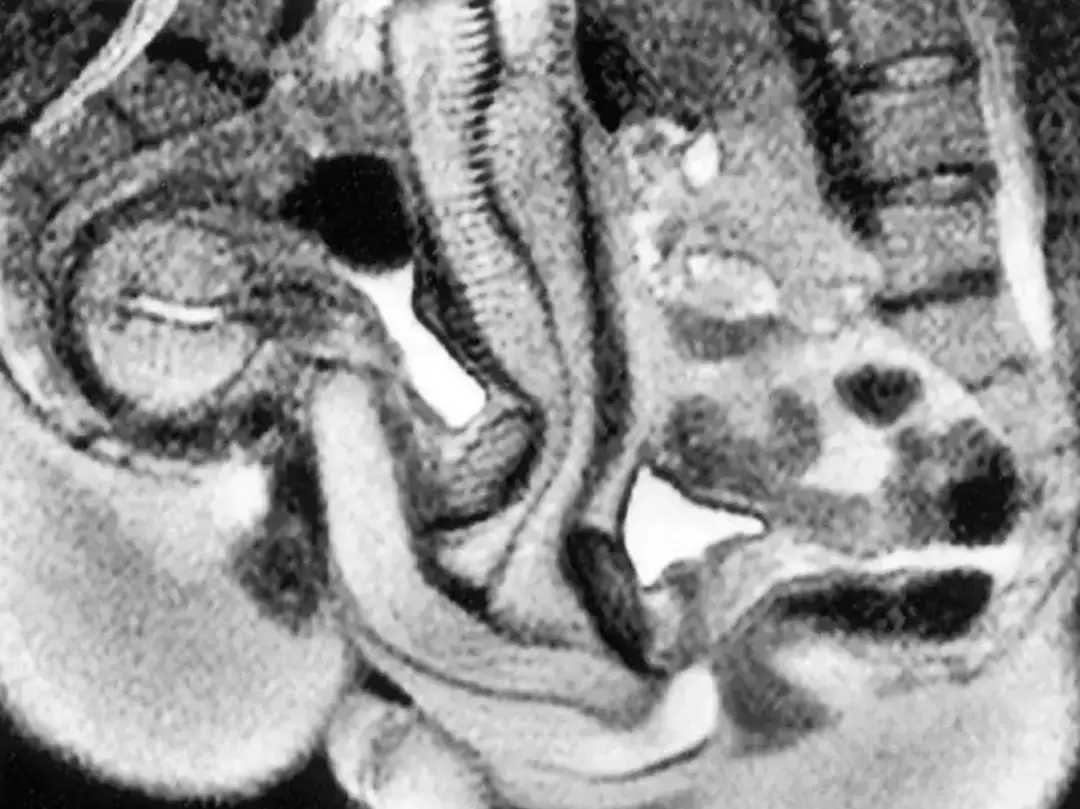

The study, published in a British Medical Journal entry in 1999, revealed that ‘taking magnetic resonance images of the male and female genitals during coitus is feasible and contributes to understanding of anatomy’.

The study detailed the findings: “The images obtained showed that during intercourse in the ‘missionary position’ the penis has the shape of a boomerang and 1/3 of its length consists of the root of the penis.

“During female sexual arousal without intercourse the uterus was raised and the anterior vaginal wall lengthened. The size of the uterus did not increase during sexual arousal.”